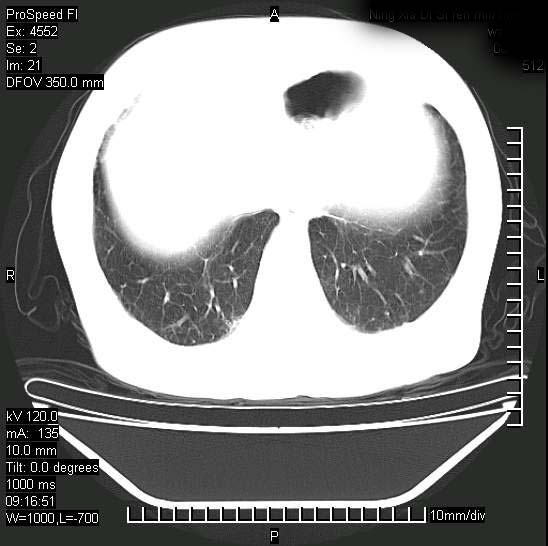

今天ct

短短几天内,病变范围明显增多扩大,以左侧明显,而且双侧出现胸水,还是考虑感染.

短短几天内,病变范围明显增多扩大,以左侧明显,而且双侧出现胸水,我更多考虑左侧中心性肺癌并并阻塞性不张及肺炎,炎症变化也太快了!

无论是肿瘤还是炎症4天的时间都发展够快的,并且还在治疗中,如果说是左肺癌那么右肺的病变不好解释,本人更加倾向于炎症,左肺舌叶支气管被痰栓或血凝块堵塞,造成阻塞性肺炎。